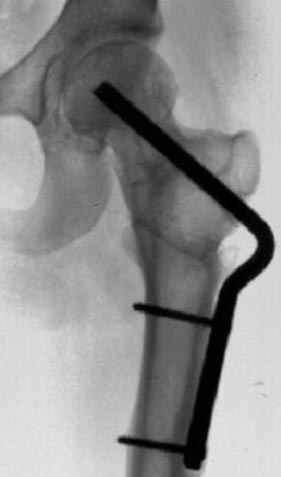

На рисунке N1 предоперационный план лечения ложного сустава шейки бедра- линия ложного сустава, угол и направление введения импланта, клиновидная остеотомия в градусах и миллиметрах, второй снимок после коррекции, расчет, на сколько удлиняется конечность и размеры импланта;

N3 рисунок окончательный снимок, после операции моя рентгенограмма должен выглядеть примерно как эта картина. На N4 снимке клин перед удалением; N5 послеоперации 3 нед.; N6 окончательная рентгенограмма.

(доложен в Ст. Петербурге 2003 и в Москве 2004)

варус при проксимальном отделе 95 градусной пластиной.